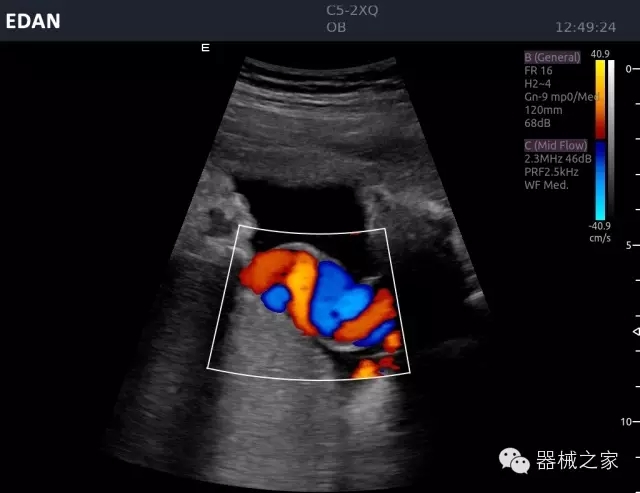

經典產品:Acclarix AX8

臨床圖片賞析

睪丸低速血流

臍帶血流

頸動脈頻譜

產品特點

·新視界、高效能、新體驗;

·別具匠心的獨特設計、創(chuàng)新工作流、強大的功能組合以滿足POC圖像的需求;

·15英寸高分辨率顯示器;

·10.1英寸防指紋觸摸屏;

·獨一無二的觸控式軌跡球;

·超聲模塊的便攜式設計;

·128物理通道;

·UPS持續(xù)供電;

多項前沿圖像技術

·復合成像 波束合成 頻率復合 噪聲抑制等;

穿刺針增強技術

·顯著增強針體 清晰識別結構、位置等比鄰關系;

多種成像模式

·梯形成像 寬景成像 3D成像 特征成像等;

CFDA注冊證編號

·粵械注準20152230912